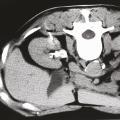

Néphrectomie totale ou partielle dans le cancer du rein ?

Publié le 20 Janvier 2018 || La Revue du Praticien || 68(1):48-50

Le traitement des masses rénales localisées est chirurgical et consiste en leur exérèse complète via l’ablation du rein dans son ensemble (néphrectomie totale) ou l’exérèse élective de la tumeur en préservant l’organe (néphrectomie partielle).Pendant de nombreuses années, la néphrectomie totale élargie a été le traitement de…